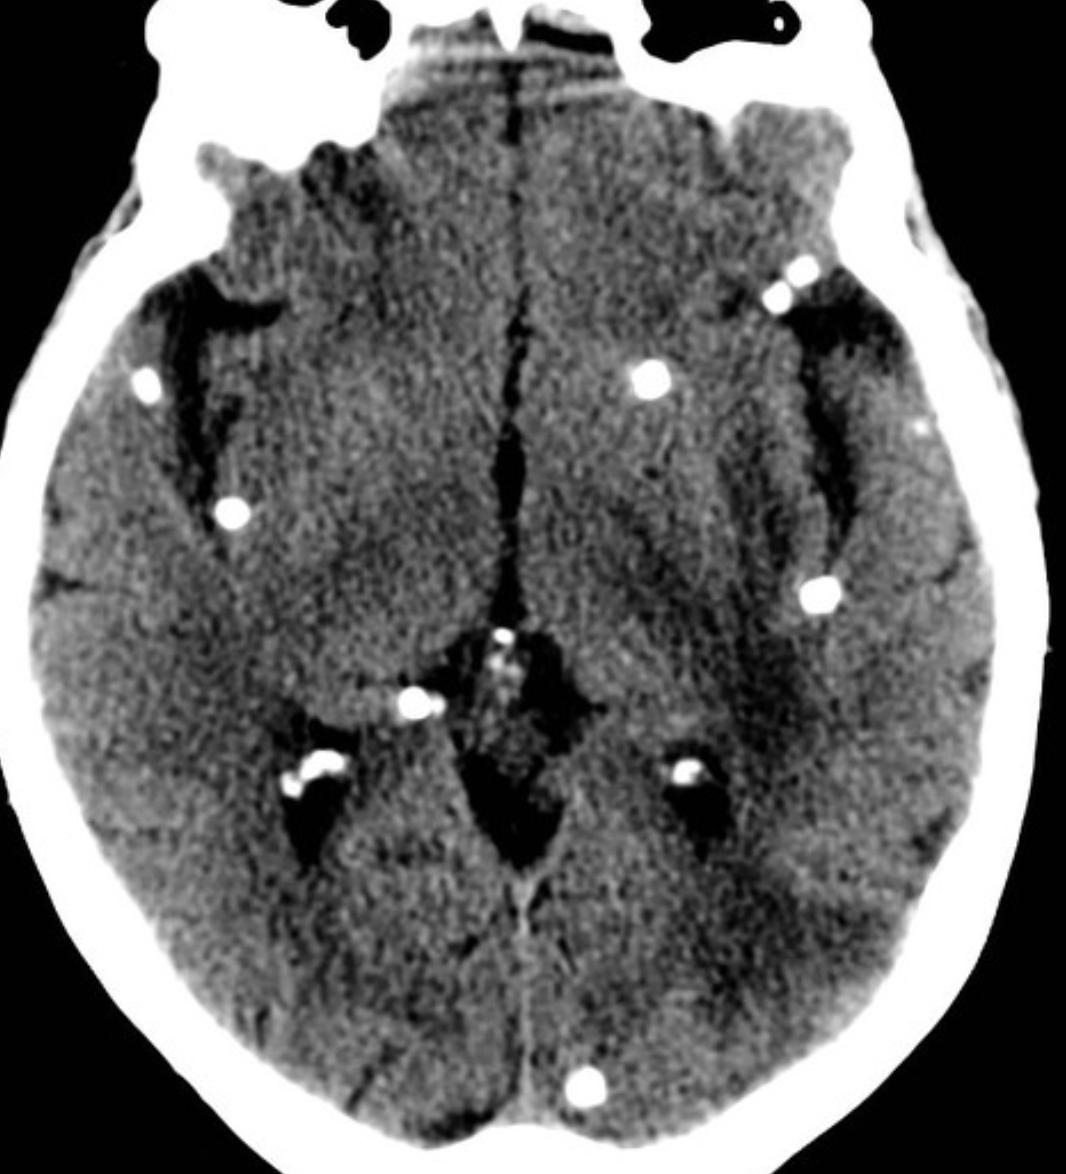

Most common CNS infection in HIV patients.

Caused by Toxoplasma gondii.

Reservoir in CATS.

Immunocomprimised : Fulminant CNS disease. Basal ganglia, Corticomedullary junction. solitary or multiple ring enhancing lesions with marked surrounding edema. Eccentric target appearance. After treatment lesions may calcify or haemorrage.